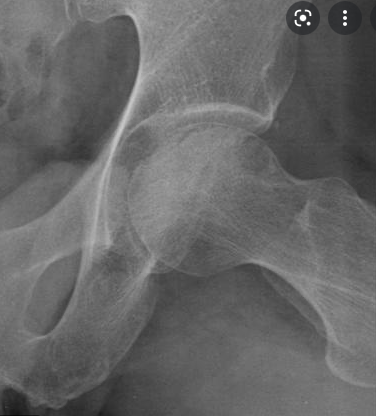

Wat is een belangrijk radiografisch teken van femurkop osteonecrose?

Spontane subchondrale fractuur = crescent sign

Wat zien we hier?

Crescent sign